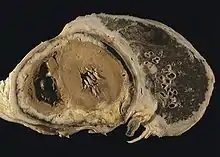

Mesothelioma is a type of cancer that develops from the thin layer of tissue that covers many of the internal organs (known as the mesothelium).[10] The area most commonly affected is the lining of the lungs and chest wall.[1][3] Less commonly the lining of the abdomen and rarely the sac surrounding the heart,[11] or the sac surrounding the testis may be affected.[1][12] Signs and symptoms of mesothelioma may include shortness of breath due to fluid around the lung, a swollen abdomen, chest wall pain, cough, feeling tired, and weight loss.[1] These symptoms typically come on slowly.[2]